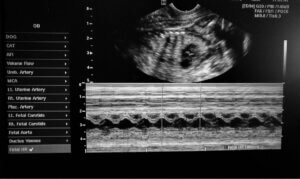

This is an exceptionally rare clinical condition, and so it’s very difficult to gather enough information for pinpointing its exact cause. It’s believed that cyclopia is caused by genetic faults or the ingestion of toxic agents by the mother during pregnancy.

The vet who attended the cyclops dog specifies that the pregnant female dog probably ingested toxic elements before giving birth. Moreover, it was an elderly female dog, and so its fertile capacity was naturally reduced over time. All these factors taken together could have led to this interesting development.